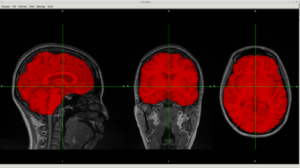

それ以前に当方、DTI-FA map を非線形変換FNIRTで標準脳地図に載せる程度のことはできていました(2009年頃から取り組んできた)。

fslmaths で標準脳segmentationを領域ごとに切り分け、0/1マスク化して、 DTI-FA画像に掛け合わせて、fslstats -M でFA値を取り出す程度をしていまし た。